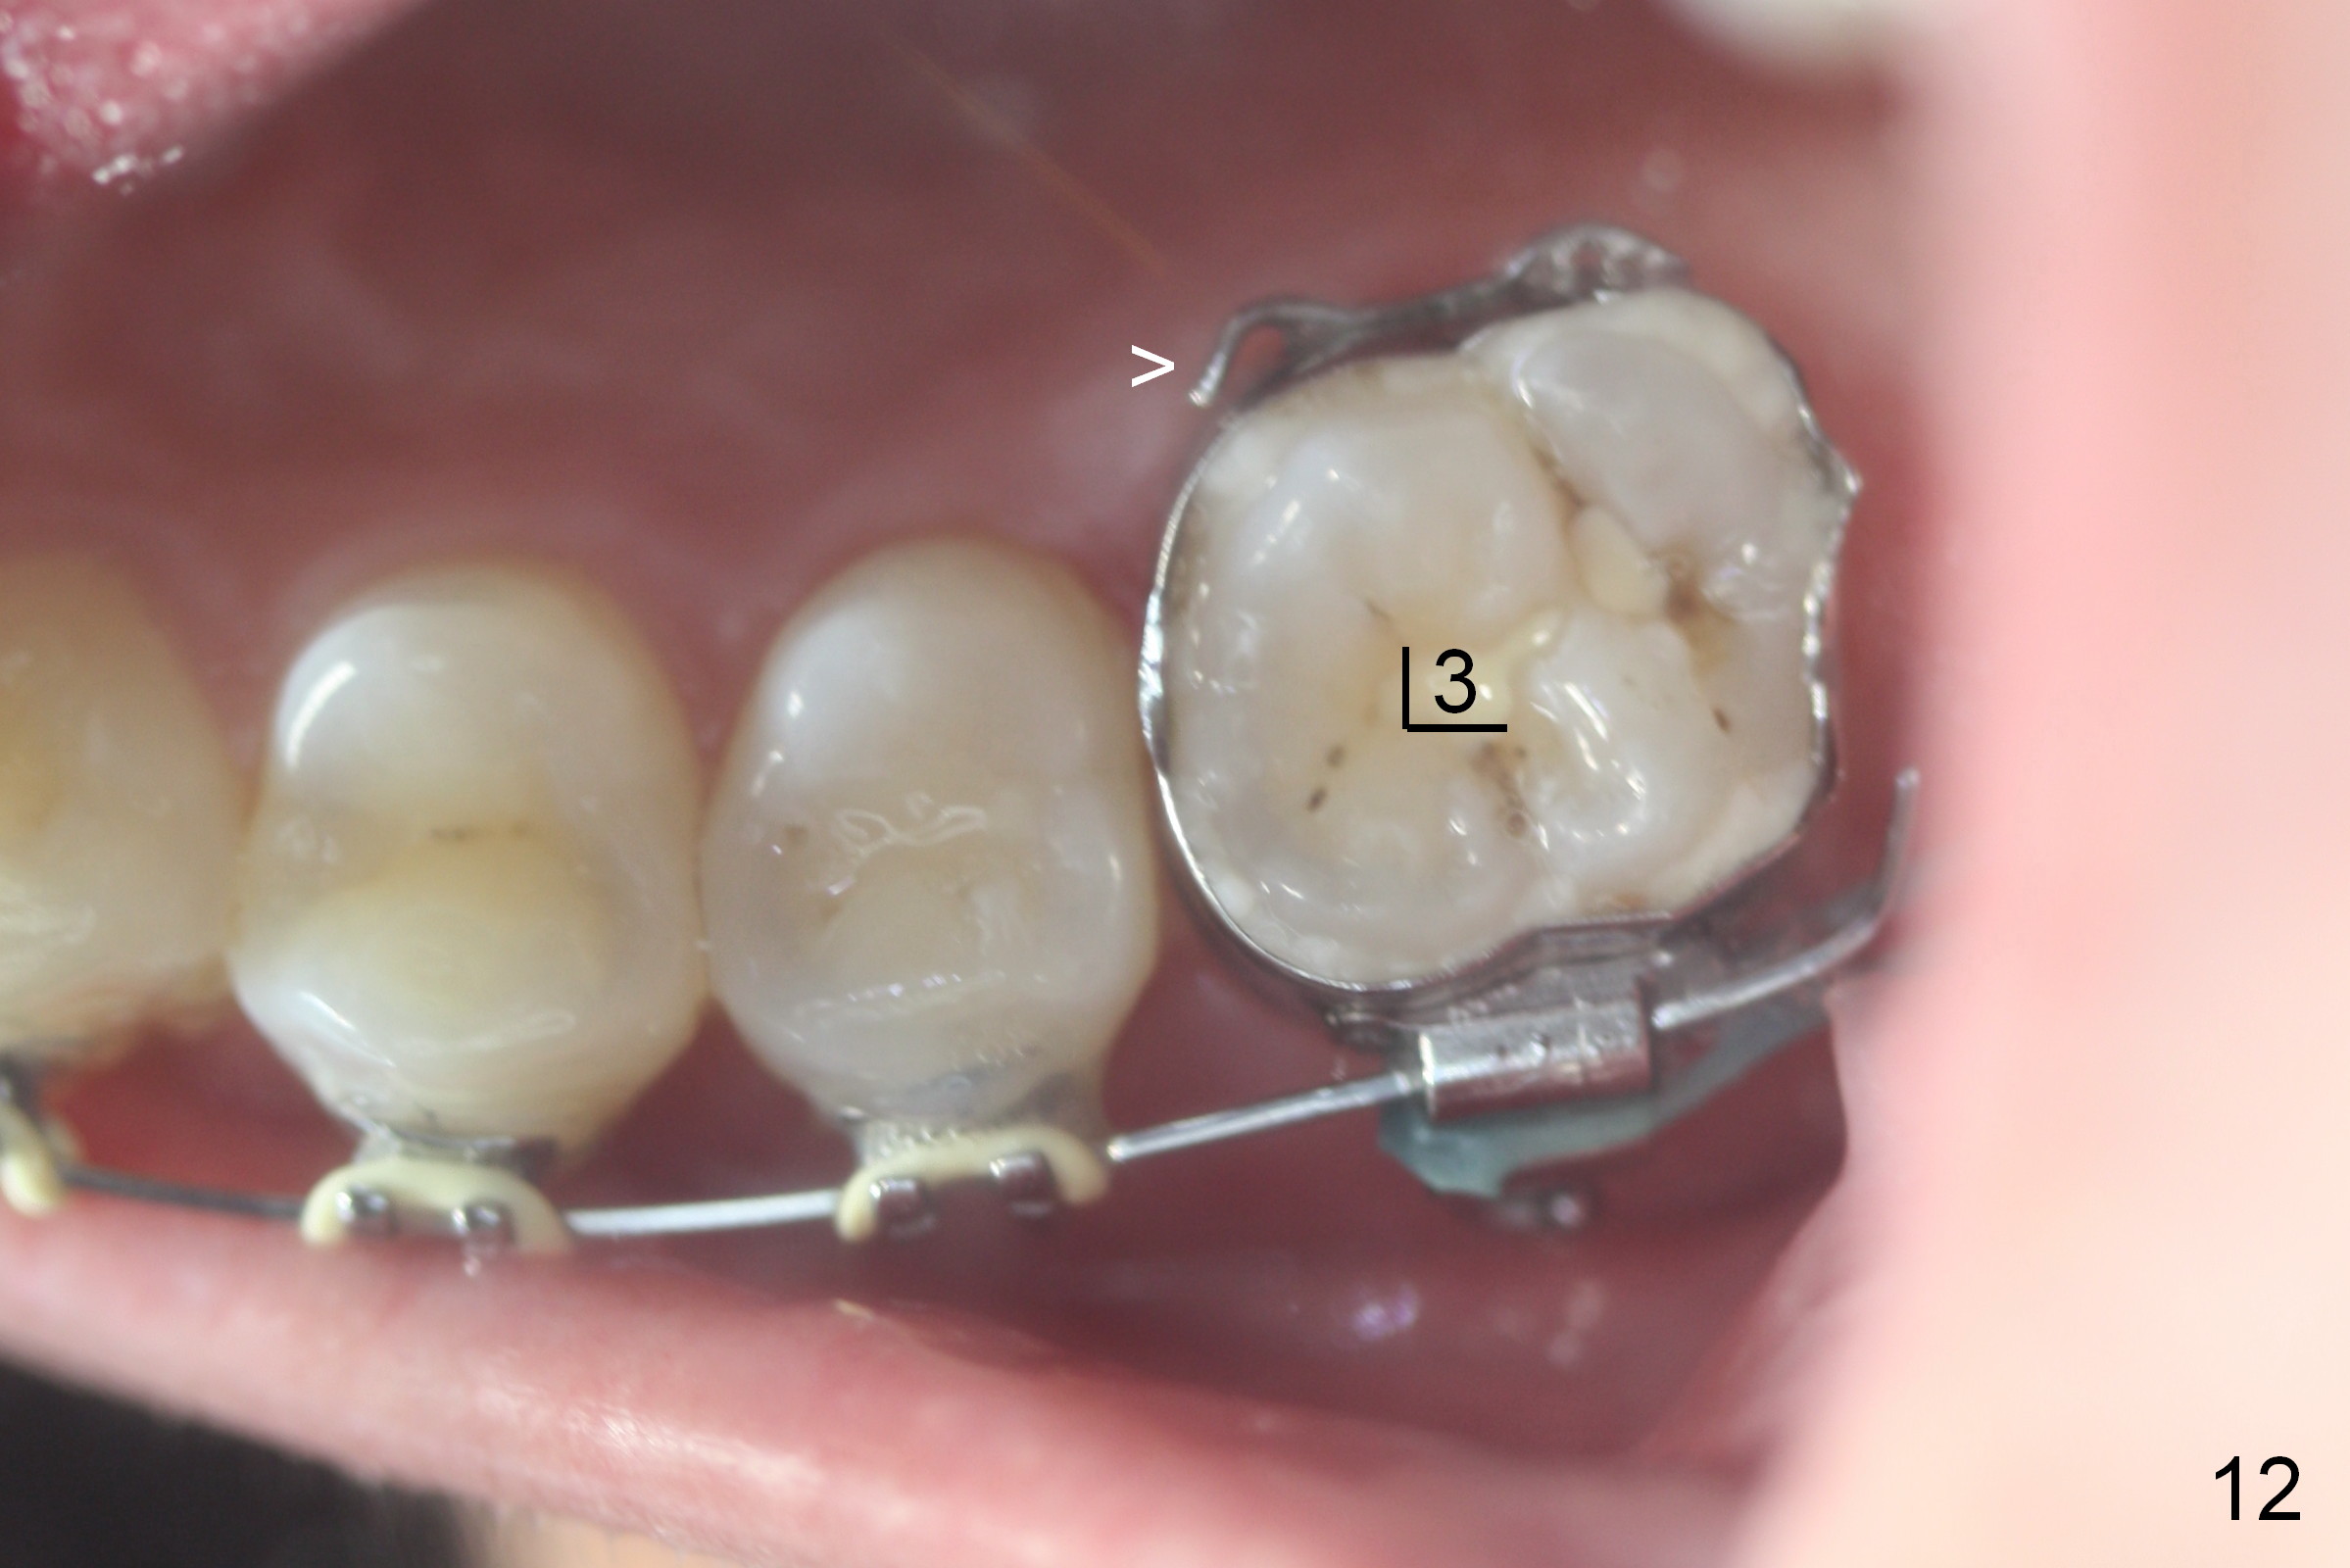

Two weeks later, it appears that U3s do not move distal (Fig.10,12), whereas the lower teeth do (Fig.11,13). Power chains change to 2 with grey ones. If no more change occurs in 1 week, change to next wires with power chains x 4 with one end attached to the lingual cleat (Fig.10,12 arrowheads) so that U3s may evenly (buccal and palatal) move distal. If LL3 keeps moving much faster than LR4, switch the closed coil springs.